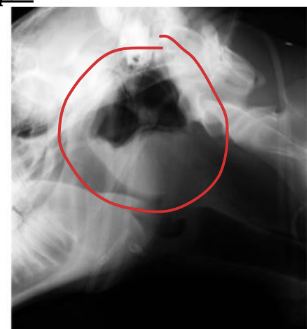

This is a latero-lateral view of the caudal part of the head. What is circled?

A

Guttural pouch

* Should be translucent

* Is in part radiopaque due to enlarged retropharyngeal LN bulging into the base of the guttural pouch